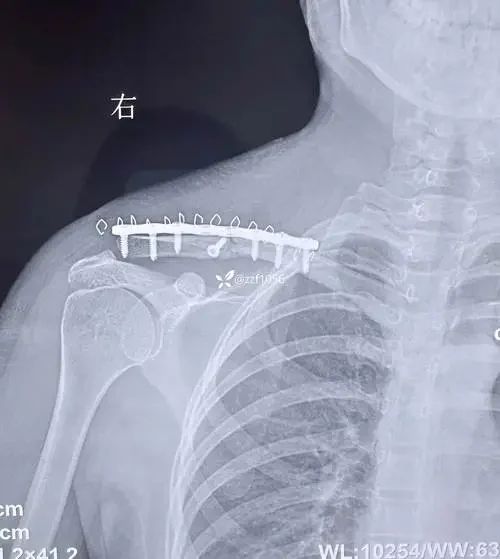

本文提供了全面的锁骨骨折与肩胛骨骨折综合管理指南,涵盖从诊断、治疗到康复的各个方面。无论是医疗专业人士还是患者,都能够通过这份指南了解如何有效处理和管理锁骨及肩胛骨骨折,以促进更快康复和减少疼痛。